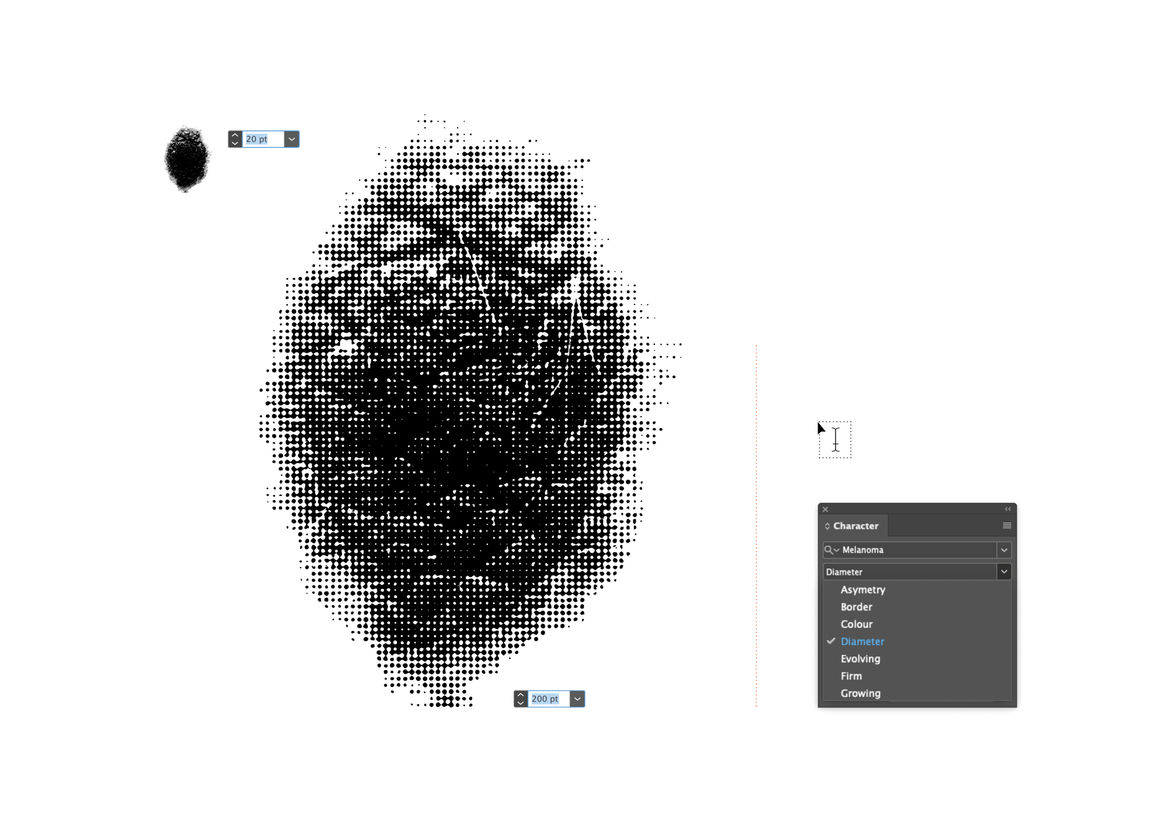

We created a usable font, made up of seven glyphs of a single character - the full stop. Each glyph was designed in partnership with New Zealand medical professionals to accurately represent one of the visual symptoms of Melanoma. When viewed at a small size, the glyphs all look like slightly misshapen full stops. But as point size increased, more and more detail is revealed in each character, until the true nature of each spot is impossible to ignore.

These seven simple characters could turn any piece of design or messaging into a melanoma awareness campaign, simply by swapping out their full stop for ours.